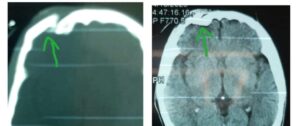

حيث تبين من الفحص المبدئى للشاب المصاب وبعدعمل الفحوصات والاشعات اللازمةعلى الفورأنه يعانى من كسور بعظام الجمجمة مع كدمات بالمخ وغيبوبة وسحجات بالوجه والرقبةوتبين أيضا أنه مصاب بنزيف متعدد بالمخ “نزيف خارج الأم الجافيةو نزيف تحت الأم الجافيةونزيف داخل أنسجة المخ”

واضاف ” ناجى” أنه في ظل التناغم والتعاون بين اقسام المستشفى على الفور بدون إنتظار أي إجراءات روتينية يتم تحضير المصاب لدخول العمليات ويأتي دور قسم جراحة المخ والأعصاب برئاسة الدكتور / إبراهيم الغريب لرفع الكسر المنخسف وتفريغ التجمع الدموي حول أنسجة المخ بينما يستعد إستشاري جراحة الوجه والفكين الدكتور/ محمد الليثى لعمل تثبيت للكسر بالفك وتتكلل جهود الفريقين بالنجاح ويخرج المصاب من جناح العمليات لغرفته بعد الاطمئنان على حالته.